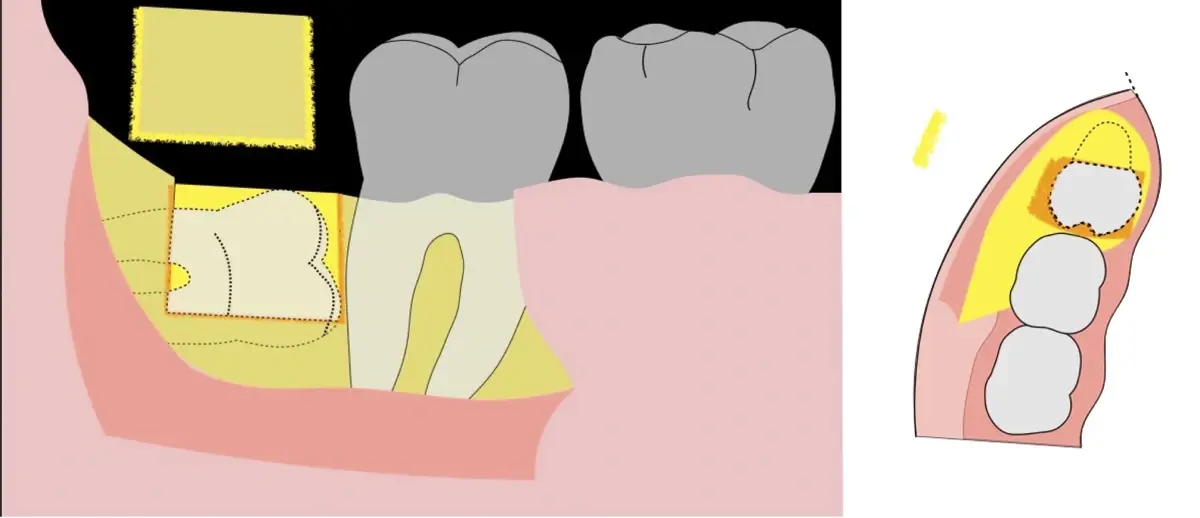

Es imprescindible conocer la ubicación de la tercera molar. Se puede emplear, adicionalmente a la evaluación clínica, herramientas radiográficas (panorámica y periapical) y tomográficas (Cone beam) para determinar la posición, grado de retención y proximidad a estructuras vecinas de riesgo como el nervio dentario inferior y así evitar lesiones (Figura 1).